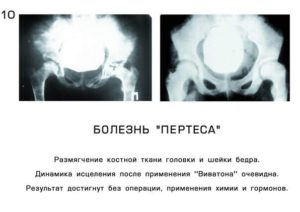

Главным способом диагностики данного заболевания является рентгенография. Используют исследование в стандартных проекциях и проекции Лауэнштейна. Исследование помогает определить степень разрушения и состояние сустава, а также определить стадию патологии.